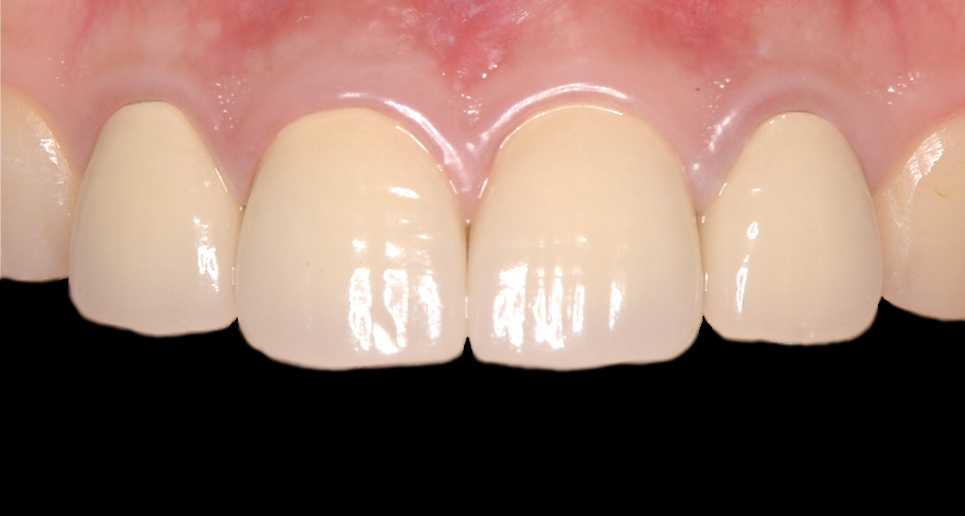

メタルボンドの治療例

患者さんは古いかぶせ物の虫歯を気にして来院しました。

①上顎左右中切歯にメタルボンド(セラミック)をセットしました。

メタルボンドの治療例

患者さんは古いかぶせ物の虫歯を気にして来院しました。

①右上側切歯~左上側切歯の4本にメタルボンド(セラミック)をセットしました。